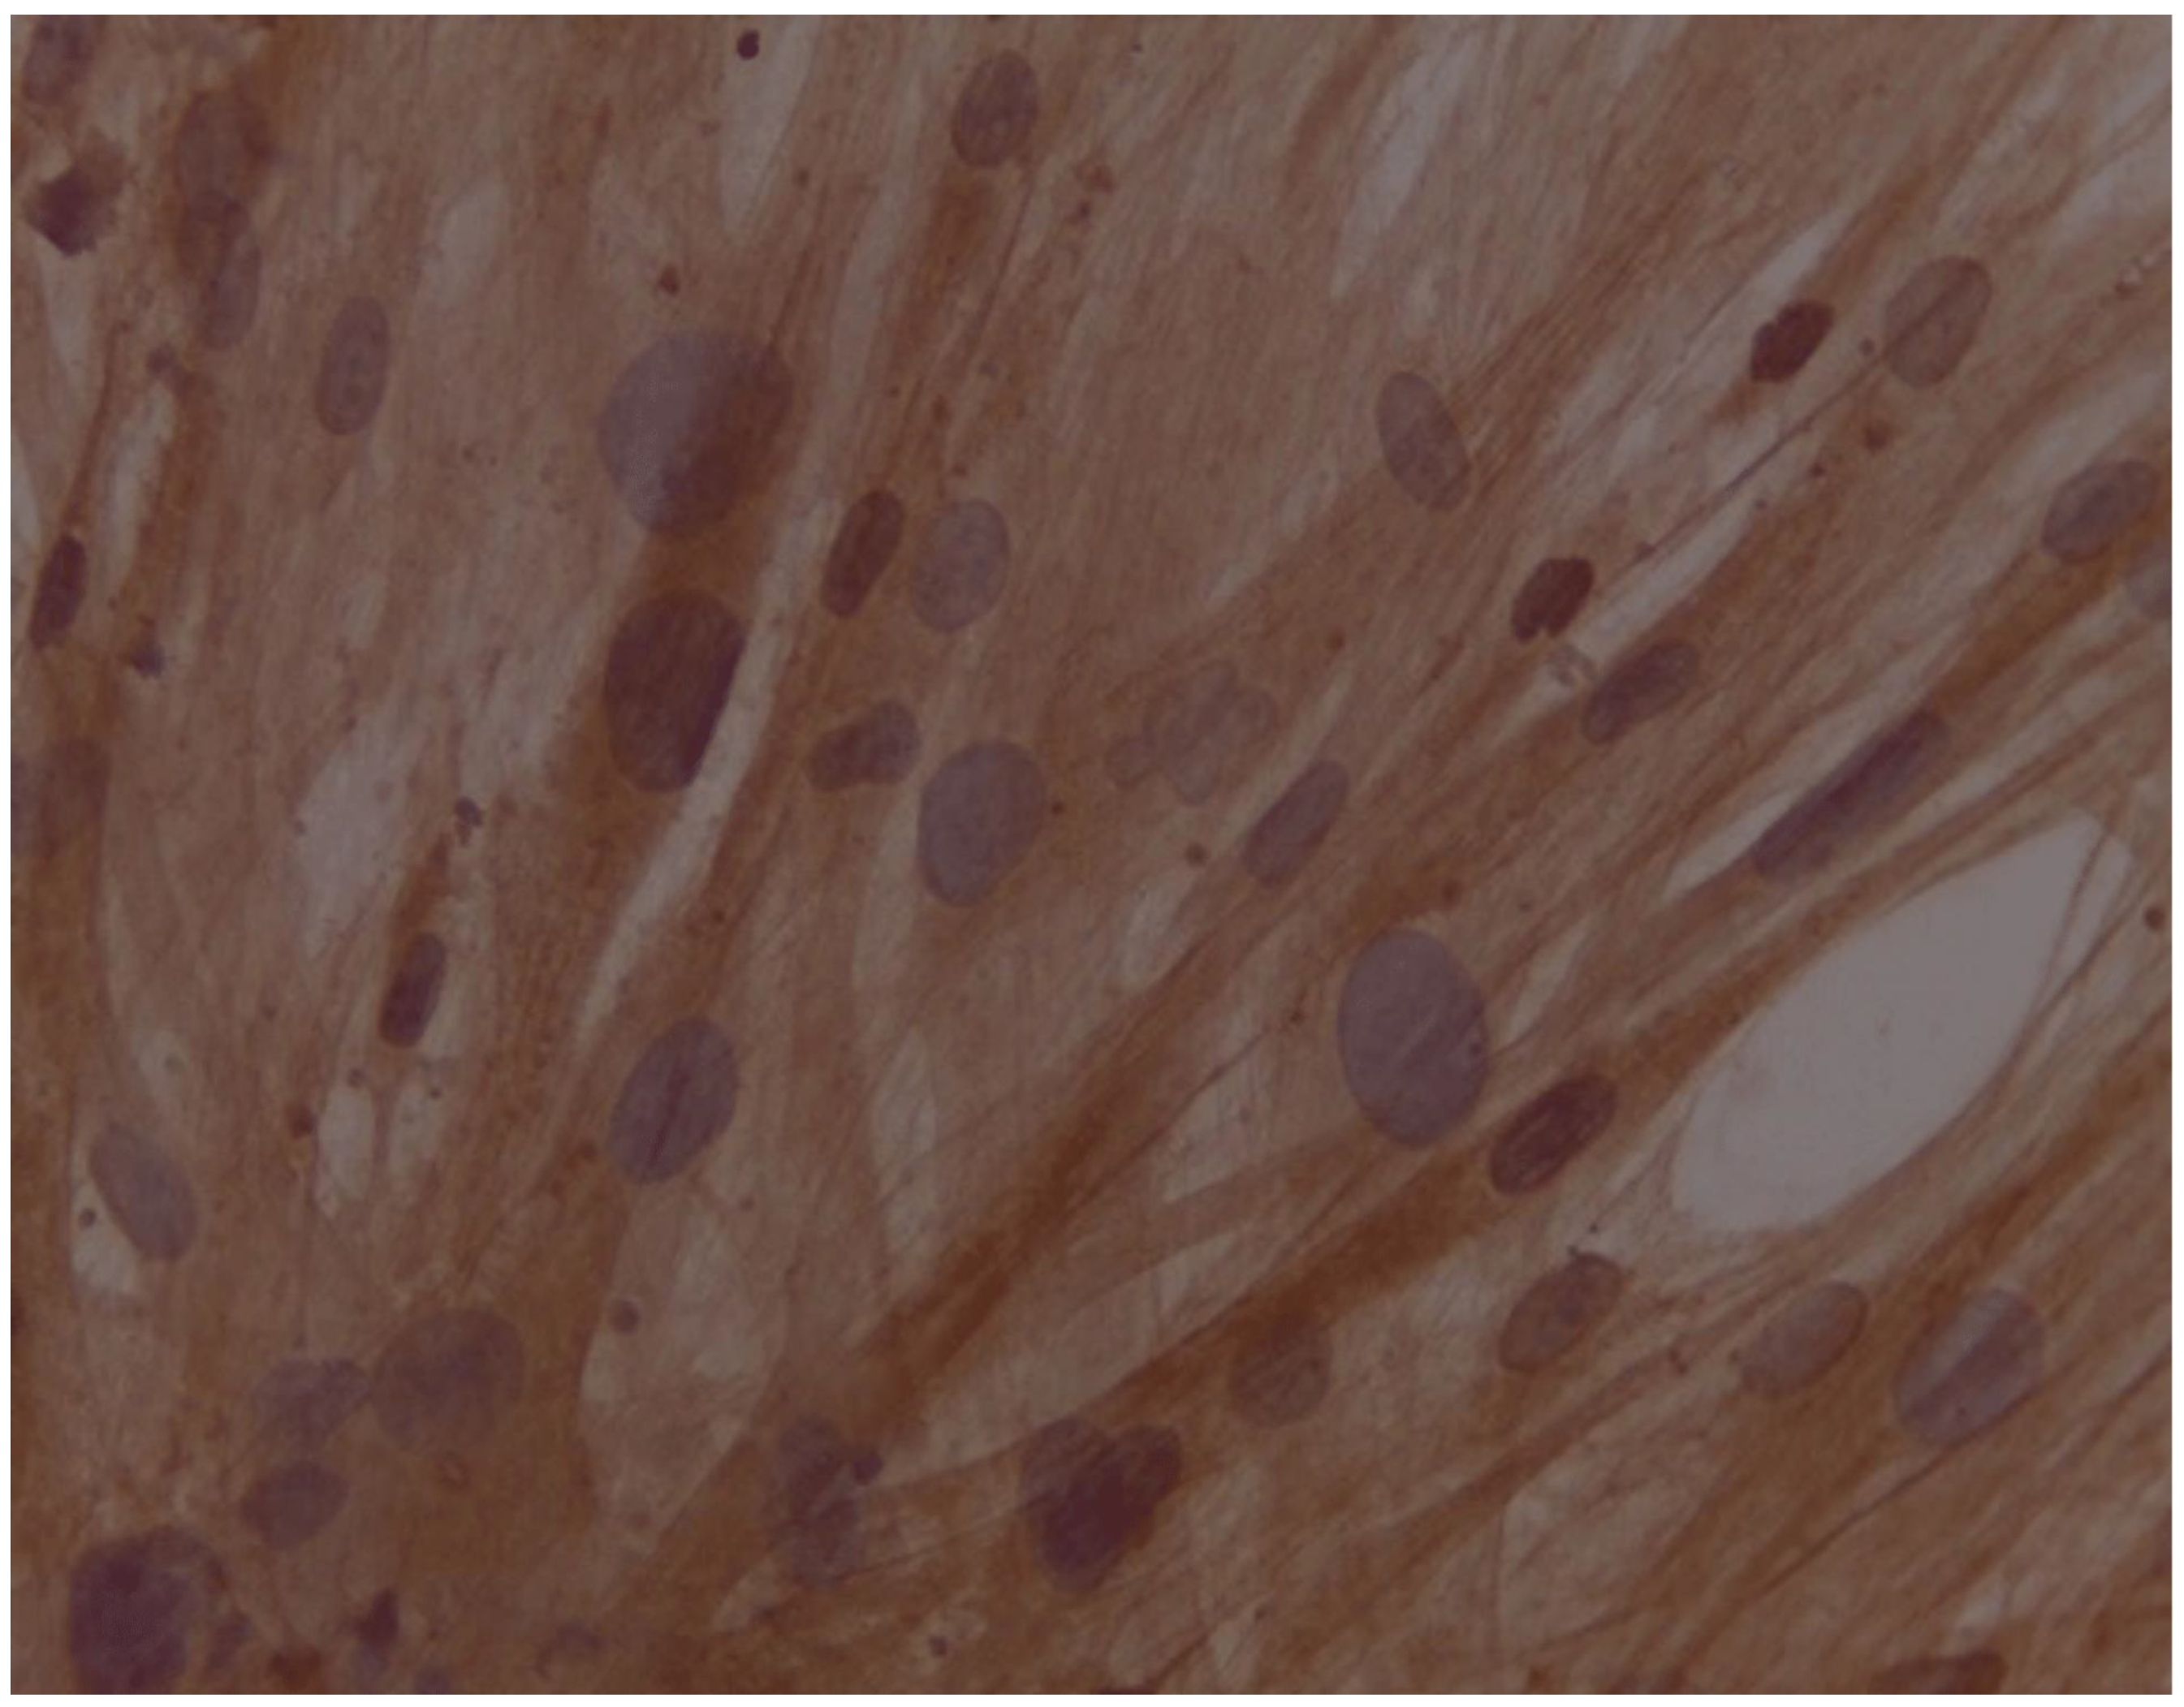

Assessment of expression of cardiomyocyte-like cells differentiation marker Troponin by Immunocytochemistry